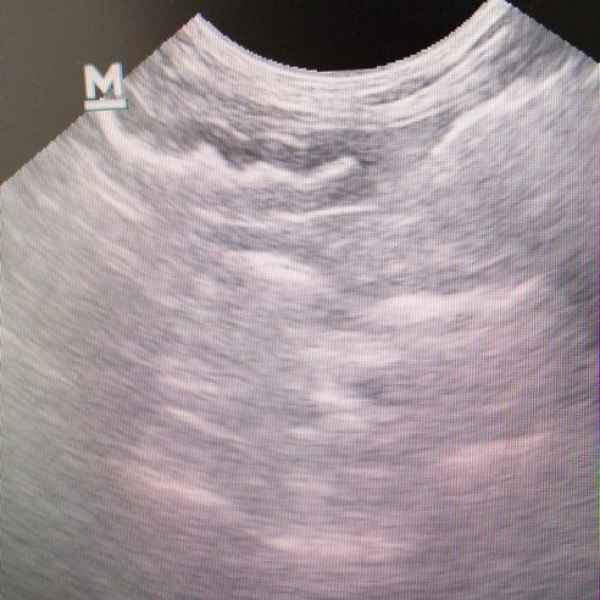

Знакомьтесь — это наш постоянный пациент Лосось. Конечно, ветеринарам хотелось бы встречаться с ним только на прививках. Но, увы, кот любит слопать что-нибудь совершенно несъедобное. Год назад ему уже делали две операции по извлечению инородных тел из кишечника. И вот опять хозяева рыжего вызвали бригаду врачей на дом. Лосось был в угнетённом состоянии. После УЗИ и анализов был поставлен диагноз: острое воспаление ЖКТ. К счастью, интенсивная терапия помогла, и кот полностью восстановился.

Кот Феликс, поступил с неукротимой рвотой, после проведения ультразвукового исследования был поставлен диагноз: линейное инородное тело в желудочно-кишечном тракте.Хирургами нашей клиники проведена операция по удалению инородного тела. Сейчас Феликс идет на поправку и близок к полному восстановлению.